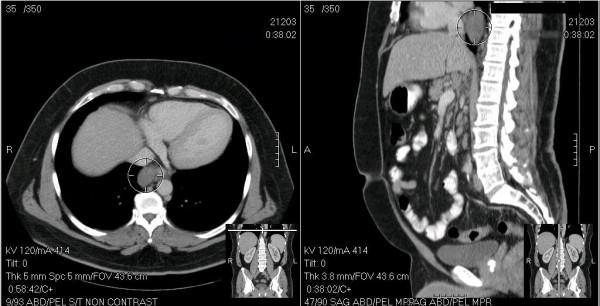

Castleman's disease (CD) or angiofollicular lymph node hyperplasia is a rare spectrum of lymphoproliferative disorders. CD tumors are commonly localized in the mediastinum and are usually asymptomatic. The mainstay of treatment is surgical resection and has typically been performed using open thoracotomy. Few reports in the literature describe video assisted thoracoscopic resection of these tumors. The differential diagnosis for mediastinal masses is extensive, and CD tumors, although uncommon, should be considered. We describe a case report of a posterior mediastinal Castleman's tumor adherent to the esophagus, which was resected thoracoscopically and review the literature.

卡斯特曼病(CD)或血管滤泡性淋巴结增生是一种罕见的淋巴增殖性疾病谱。CD肿瘤通常位于纵隔,通常无症状。治疗的主要方法是手术切除,通常采用开胸手术进行。文献中很少有报道描述电视辅助胸腔镜切除这些肿瘤。纵隔肿块的鉴别诊断范围广泛,CD肿瘤虽然不常见,但也应予以考虑。我们描述了一例与食管粘连的后纵隔卡斯特曼肿瘤的病例报告,并对文献进行了回顾,该肿瘤通过胸腔镜进行了切除。